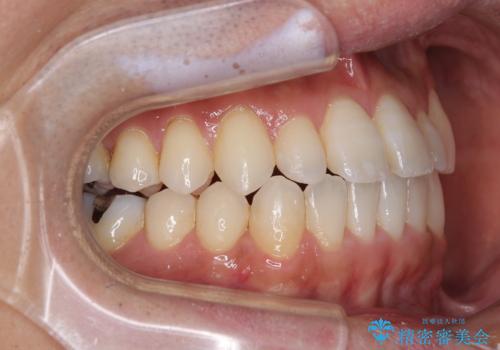

内側に引っ込んだ歯を治したい インビザラインの矯正治療

- 前歯のデコボコとクロスバイトを治したいとのことで来院された患者様です。

上下顎ともに歯列全体の側方拡大とIPR(歯と歯の間を削る)によってデコボコとクロスバイトが解消するように設計し、インビザラインにより治療を行うこととしました。

反対咬合特有の治療途中の前歯の干渉が長く続き、治療中に食事をとりにくく、ご迷惑をおかけしました。

前歯の咬み合わせの調整などを行い、安定した咬み合わせに仕上げることができました。